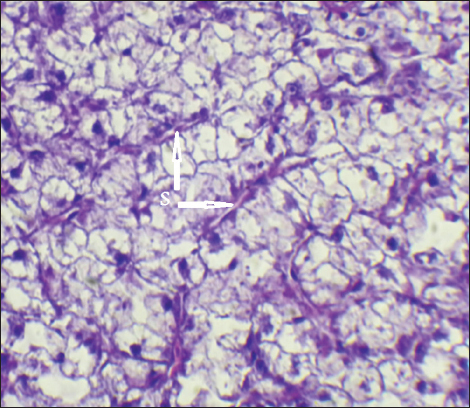

The result of histopathological alteration of the liver revealed degenerative and necrotic changes in liver tissue distinguished by pyknosis with the existence of necrosis in cells (Figs. 14 and 15) also, the result revealed dilation of the sinusoids with cytoplasmic vacuolation (Fig. 16).

Fig. 16. Histopathological sections of liver of C. carpio showing dilation of the sinusoids (S) with cytoplasmic vacuolation (H&E X40).

It is well known that exposure to heavy metals can cause a variety of histopathological changes (Mustafa et al., 2012). These changes may be related to the harmful effects of heavy metals on hepatocytes, as the liver is involved in the biotransformation and detoxification of various pollutants and toxicants (Arellano et al., 1999). The observed necrosis in certain areas of the liver tissue may have been caused by the fish’s overwork in eliminating the toxins from its body during the detoxification process; this observation is consistent with the findings of Rhaman et al. (2002).